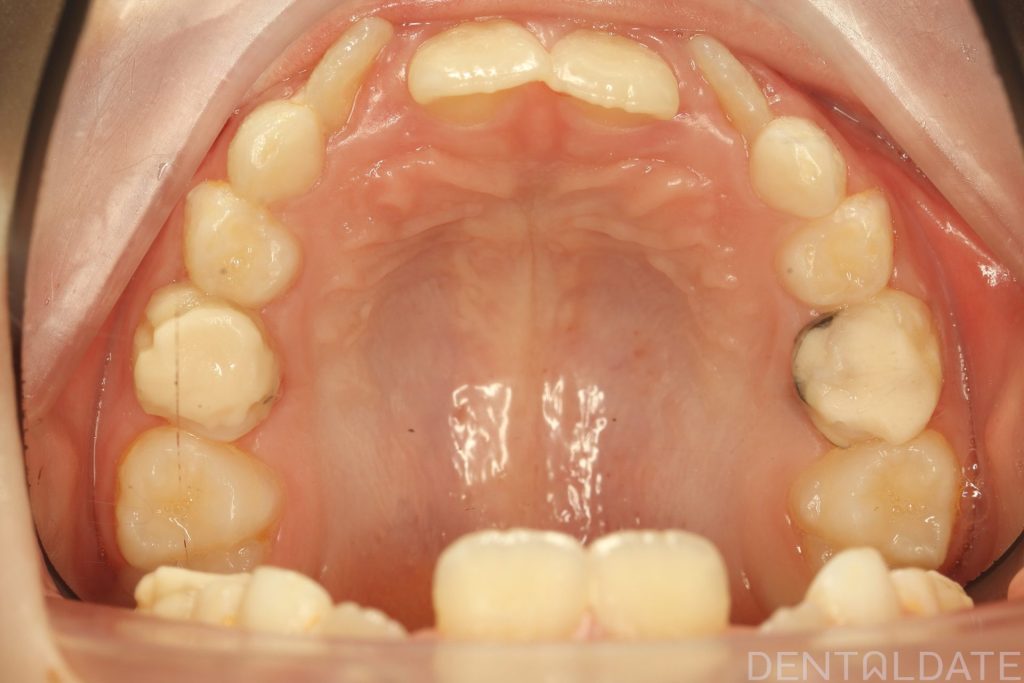

The patient had been undergoing orthodontic treatment at another clinic for 1.5 years with no significant progress.